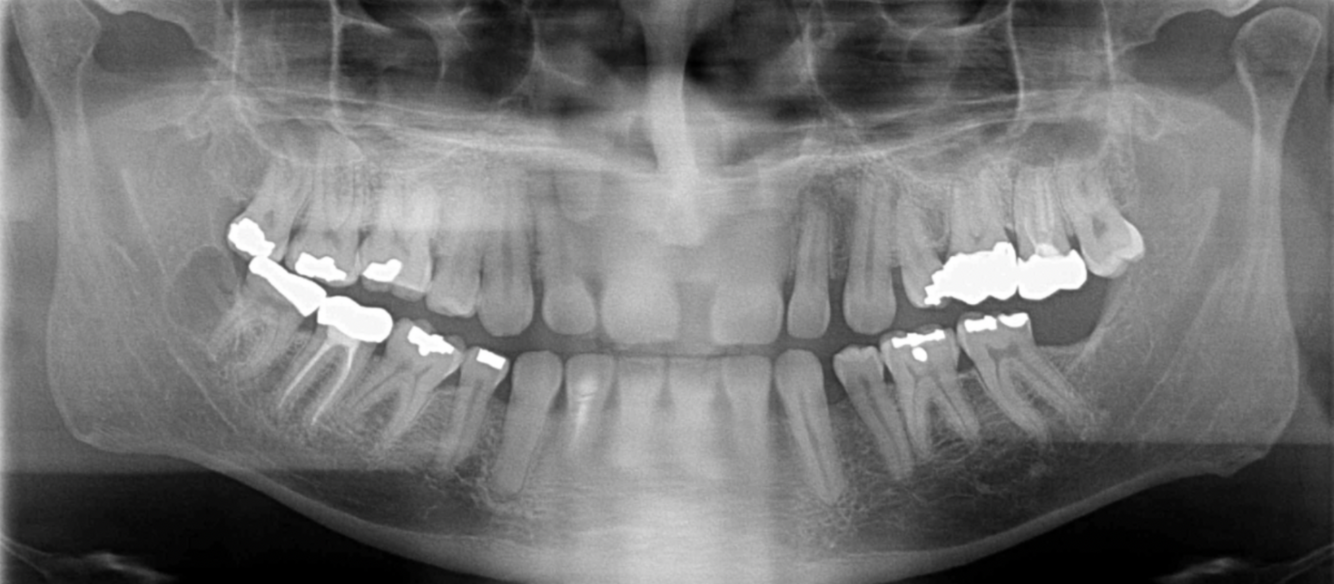

What errors can be seen in the following radiograph? What is the cause of these errors?

A

1. Anterior teeth are narrowed and blurred

2. Cervical spine is superimposed on ramus ( double real image of cervical spine)

Cause: Too far forward